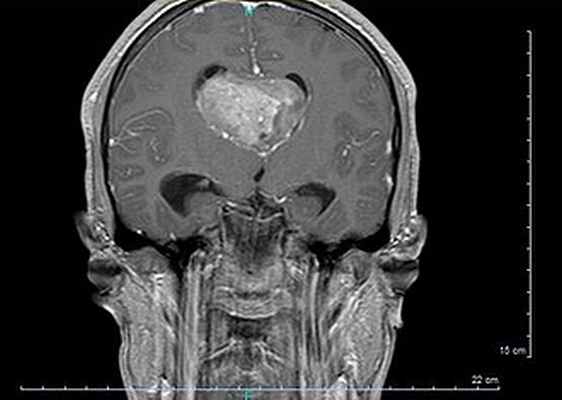

МРТ головного мозга, коронарный срез, последовательность повреждений Т1, большая нейроцитома правого бокового желудочка.

Диагноз ставится с помощью визуализации головного мозга, компьютерной томографии или, в лучшем случае, МРТ головного мозга, обнаруживая это гетерогенное образование с тремя основными компонентами (ткань +/- кистозный и кальций) с частичным усилением при введении контрастного вещества.

Это позволяет изучать взаимосвязи с функциональными областями мозга (в частности, столбом свода, одним из компонентов цепи Папеза, отвечающим за антеградную память), сосудистой системой (сетью глубоких вен), а также воздействие опухоли на мозг (массовый эффект из-за гидроцефалии , отека , кровотечения , поражения…).